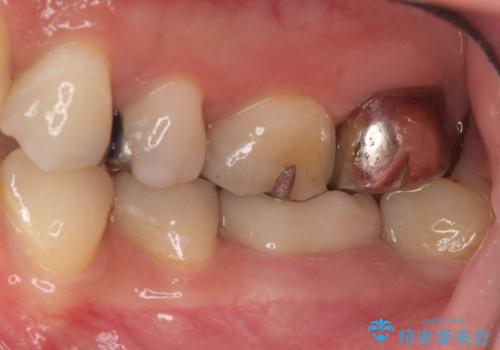

- 下顎の銀歯と、かぶせ物が外れたままになっている歯の治療を主訴に来院されました。

左下の奥歯はかぶせ物が外れて、土台が露出している状態でした。